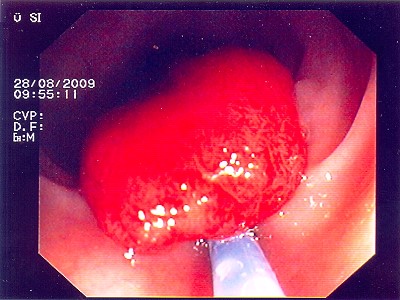

Gut sichtbarer Blutstrahl nach Abtragung eines Polypen

Sichere Blutstillung durch einen Metallclip